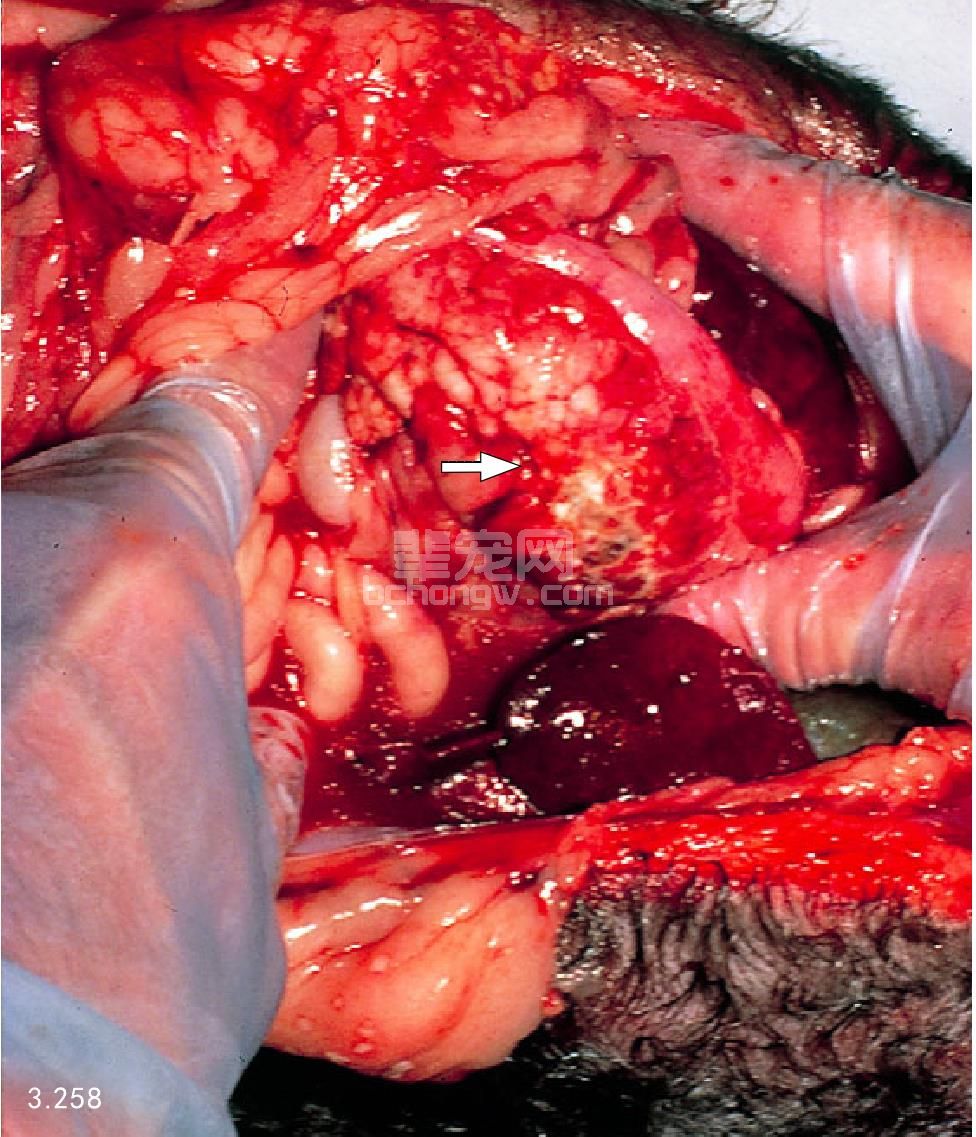

图3.258 图3.256中的犬死后剖检有严重的出血性胰腺坏死(箭头所指)。